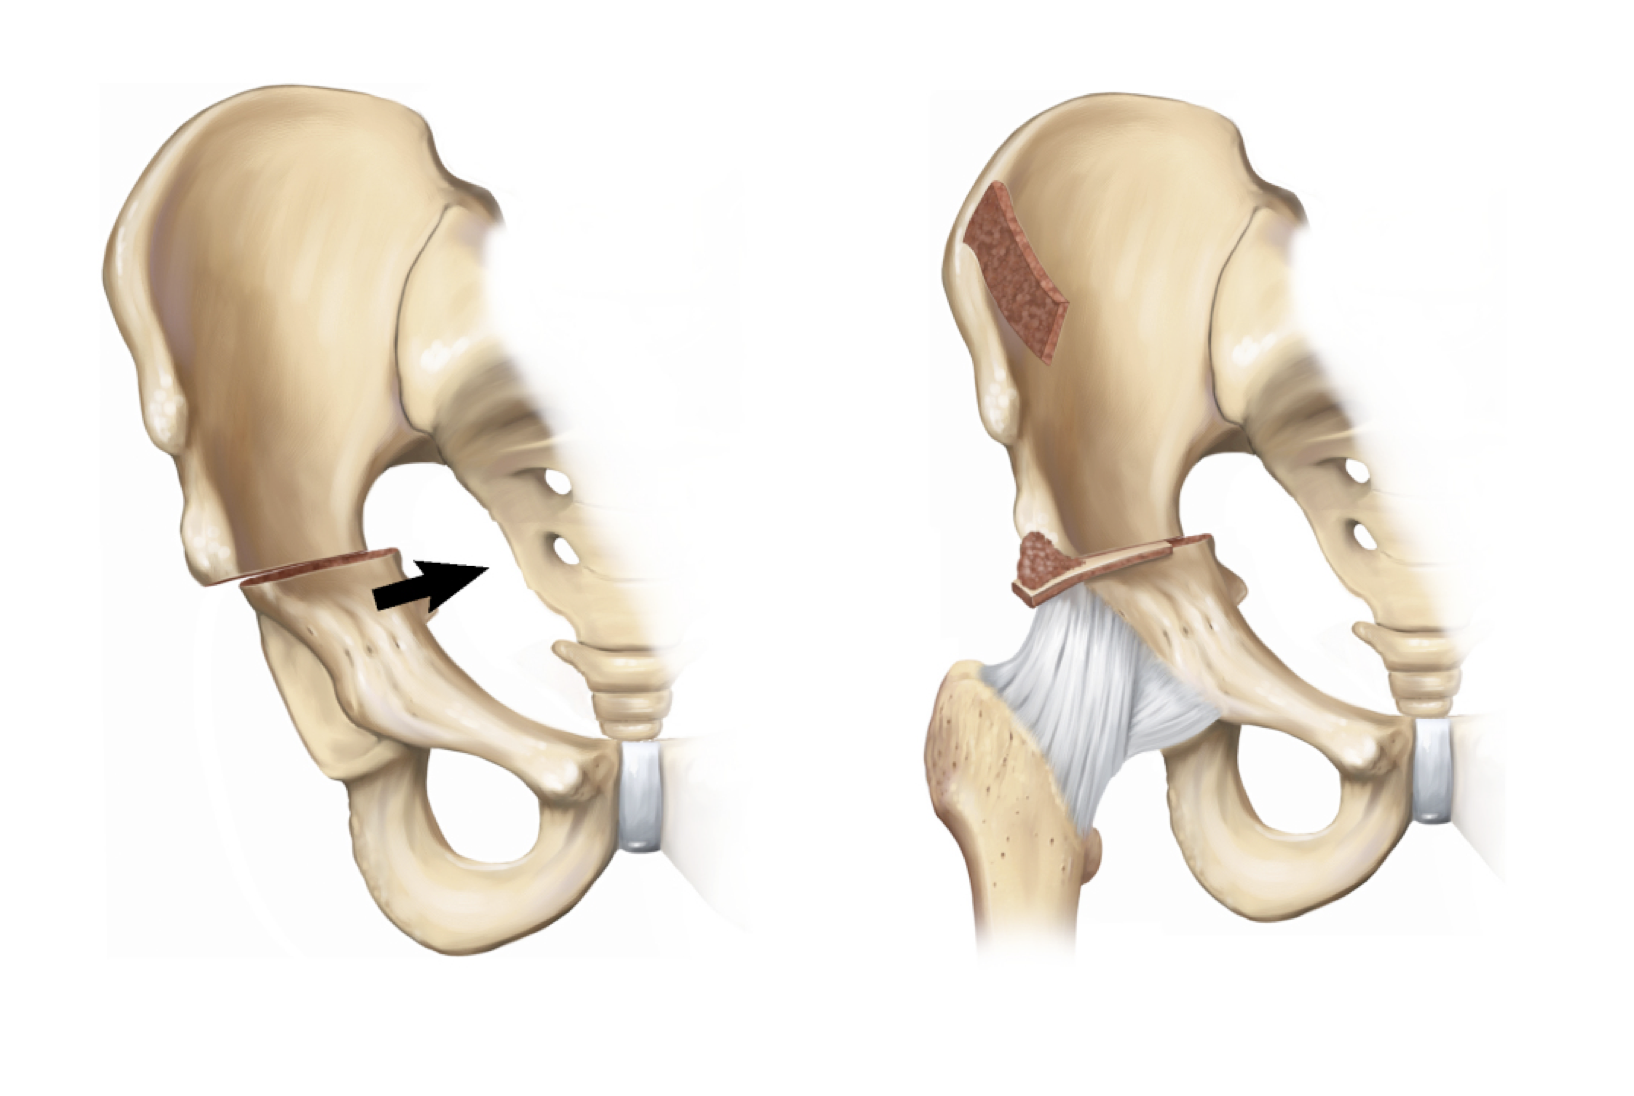

De peri-acetabulaire Ganz osteotomie is een osteotomie vlakbij het gewricht en vanuit verschillende hoeken waardoor de heupkom volledig kan worden losgemaakt. Hierna kan de heupkom opnieuw in een goede stand worden gefixeerd. Dit alles gebeurt door 1 incisie in de liesregio.

Er gebeurt een gedeeltelijke osteotomie doorheen het ischium (1), vervolgens een osteotomie doorheen de pubis (2), dan een osteotomie boven het acetabulum doorheenhet ilium (3) en tenslotte een osteotomie achterhet acetabulum (4) en deze osteotomie komt dan weer uit in de eerste osteotomie.

Belangrijk hierbij is dat de achterste pijler van het bekken intact blijft, waardoor de nervus ischiadicus beschermd wordt. Misschien nog belangrijker is dat door het intact zijn van de achterste pijler ook de bekkenring behouden blijft waardoor het bekken stabiel blijft en slechts minimale inwendige fixatie nodig is.

Correctie en nadien fixatie met 3 of 4 schroeven